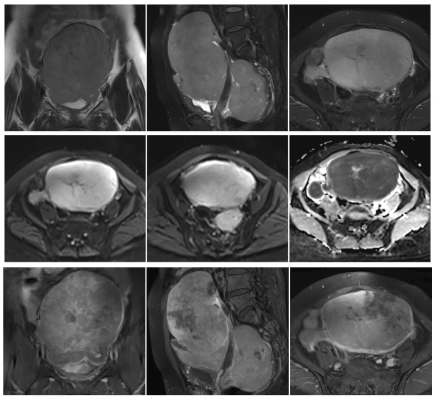

Imaging findings: there were multiple large soft tissue shadows in the pelvic cavity, and the larger ones were approximately 14.2 cm × 9.7 cm × 15.6 cm in size; the boundary was still clear. The lesions were characterized by an equal length T1 and slightly longer T2, with locally visible nodular long T2 and short T2 signal foci. The DWI signal was obviously high and the ADC signal was reduced. The part of the enhancement showed obvious non-uniform reinforcement. The uterus was imbedded, the normal musculoskeletal structure was unclear, and the posterior part of the lesion was closely related to the rectum, as shown in figure 1.

Figure 1. A 64-year-old woman, Primary female genital system lymphoma, Pelvic MRI showed multiple soft tissue mass shadows in the pelvic, T2 coronal position, T2-fs sagittal position, T2-fs axis position. (1-3) Obviously high signal on DWI, Low Signal on ADC (4-6). The part of the enhancement showed obvious non-uniform reinforcement (7-9)